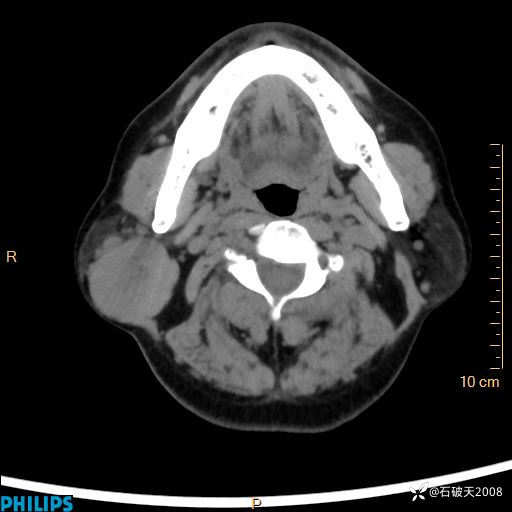

病例分享:颈部占位,一周后公布病理

男 57岁 主 诉:发现右侧颌下肿物1月余。

现病史:1月余前家属发现右侧颌下肿物。局部皮肤无红肿、热痛,无吞咽困难,无异物感,无恶心、呕吐,无头痛、头晕,无胸闷、胸痛,无发热、咳嗽、咳痰及呼吸困难。于我院行体表肿块彩超检查(2024.03.15我院)示:右侧耳下皮下软组织内低回声,未治疗。今为进一步治疗门诊以“腮腺肿瘤”为诊断收住我科,发病来患者神志清,精神可,饮食、睡眠及大小便正常,体重无明显下降。

动脉期